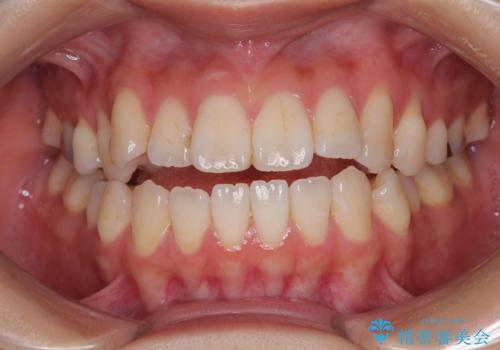

舌の突出癖が原因 インビザライン矯正による開咬改善

- 前歯の開咬を気にして来院された患者様です。

開咬の治療は、前歯を閉じるように動かすとともに、上下臼歯を圧下(骨内にめり込ませる)させることで進めて行きます。

インビザラインは臼歯の圧下を効果的に行えるため、インビザラインを用いて矯正治療を行うこととしました。